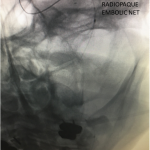

Figure 2.

Catheter angiography prior to angioplasty revealed critical stenosis (Figure 2). Angioplasty was therefore performed under local anesthesia with an embolic protection device deployed to catch any dislodged debris (Figure 3). After angioplasty, a stent was opened across the lesion to maintain long-term patency (Figure 4). Post-stent angiography showed smooth dilatation of the lesion. The patient’s aphasia continued to improve at his 6-week follow-up visit and duplex revealed no significant stenosis through the stent.